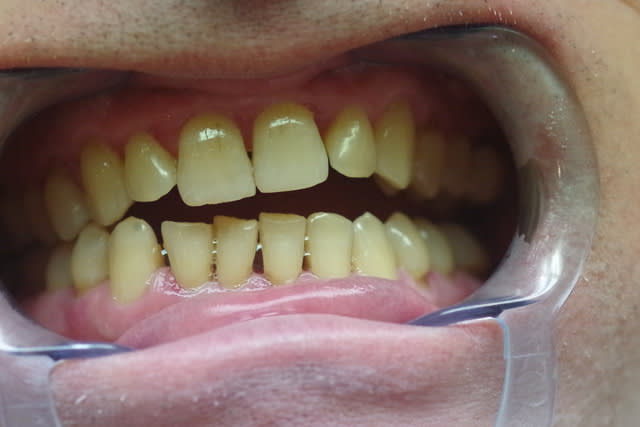

Les photos sont assez évocatrices car le plan de Fox mis à l'arcade supérieure montre nettement une divergence entre la ligne bipupillaire et le plan.

J'ai pris aussi une photo en demandant au patient de déglutir et on voit la langue qui s'interpose entre les arcades ( là où il y a béance).

Bien vu le plan de fox!

Ce monsieur a une langue très présente (photo 2) => rééducation.

La photo avec la langue a été prise au moment où j’ai demandé au patient de déglutir : le test a été révélateur car ce patient a une déglutition infantile ou primaire ( je ne connais pas très bien les termes) et pousse sa langue sur les dents.